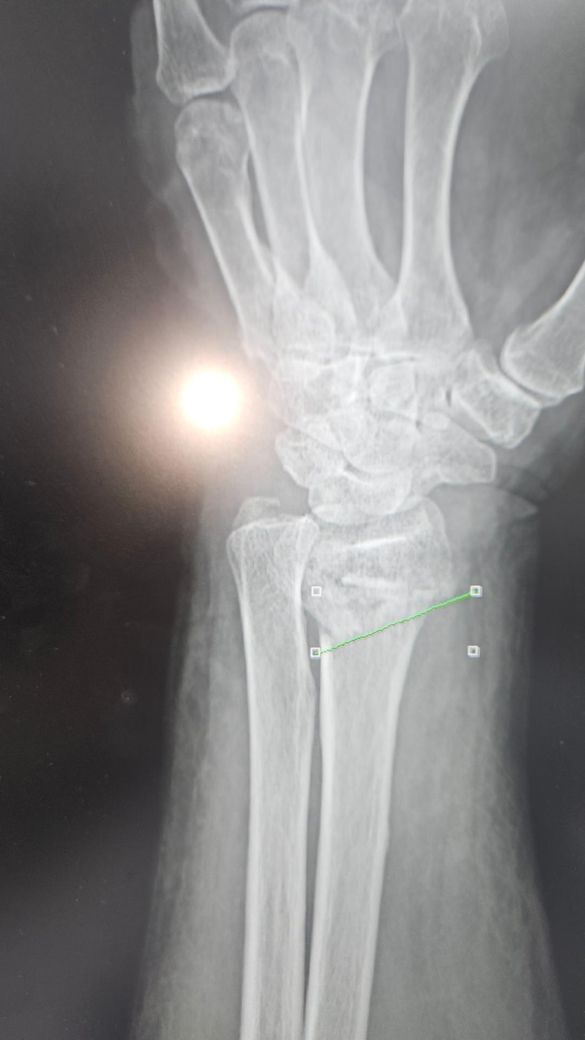

• 1번 째 사진

엑스레이상 골절부위의 어긋남이 심한편이라 병원에서 수술을 권한걸로 보입니다. 현재사용중인 탈부착형 보조기는 세척과 치료는 용이하나 86세 고령환자의 불안정한 골절을 고정하기엔 힘이 부족할수 있습니다. 처방된 약은 단순 진통제가 아니라염증과 붓기완화 목적도 있으므로 임의 중단은 피하는게 좋습니다.현재치료비용과 고정의 불확실성을 고려할때 수술이 정 어렵다면 통깁스를 통해 아예 움직임을 제한할수 있게 고정하는 방안을 담당의사와 상의하는걸 추천드립니다. 뼈가 붙지 않은 상태에서 한의원 방문보다 정형외과적 고정이 최우선입니다. 빠른쾌유를 빕니다.

엑스레이상 손목 요골 원위부 골절로 보이며, 고령에서는 정복이 유지되지 않아 변형 유합 위험이 있습니다.

반깁스를 자주 풀고 다시 고정하면 실제로 정렬이 틀어질 수 있어, 안정적 고정(깁스 유지)이 더 중요합니다.

제시된 X-ray와 경과를 종합하면 관절면을 일부 포함한 원위 요골 골절에 전위가 있었고, 정복 후에도 고정이 안정적으로 유지되지 않는 흐름입니다. 특히 반깁스를 반복하면서 정렬이 흔들린다는 점은 비수술 치료의 핵심 조건인 “정복 유지”가 실패할 위험 신호입니다. 이런 경우 시간이 지나면 부정유합으로 이어지고, 손목 변형과 회전 제한, 악력 저하가 남을 가능성이 높습니다.

지금 제시된 영상은 전형적인 원위 요골 골절로 보이며, 관절면을 일부 침범하면서 전위가 동반된 형태 가능성이 있습니다. 고령에서 흔한 골다공증성 골절 양상과 일치합니다. 정복 후 유지가 핵심인데, 현재 사진과 경과 설명상 “정복 유지 안정성”이 충분한지 의문이 있습니다.

비수술 치료의 적응은 [전위가 크지 않고, 정복 후에도 정렬이 유지되는 경우]입니다. 반면 다음 상황이면 수술을 고려하는 것이 일반적입니다. 관절면이 어긋난 경우, 등쪽으로 많이 꺾인 경우, 요골 길이 단축이 있는 경우, 그리고 정복 후에도 다시 틀어지는 경우입니다. 현재처럼 반깁스를 자주 풀고 다시 고정하면서 정렬이 반복적으로 변한다면, 유지 실패 가능성이 높습니다.

86세 고령, 뇌졸중 병력, 당뇨, 고혈압이 있는 점은 수술 위험을 분명히 증가시키지만, 최근 가이드라인에서는 “기능 요구도가 낮고 변형을 어느 정도 감수 가능”하면 비수술도 허용됩니다. 다만 이 경우에도 최소한 초기 1주에서 2주 동안은 정복 상태가 유지되는지 연속적인 X-ray 확인이 중요합니다. 3주차인데 붓기 변동과 함께 정렬 유지가 불안정하다면, 이미 부정유합 방향으로 진행 중일 가능성도 배제할 수 없습니다.